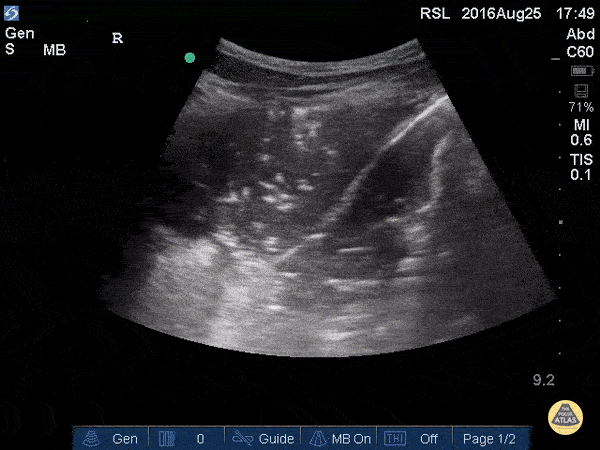

Pulmonary - Lung Consolidation with Mirror Artifact

A consolidated right upper lung can be seen above the fissure which is to the left (superior) in this image. There is hepatization of the lung with static and dynamic air bronchograms. These represent air with fluid filled alveoli around them. Dynamic air bronchograms are pathognomonic for pneumonia and represent air bubbles moving through the otherwise fluid filled tissue. Hepatization refers to lung tissue that looks like the liver and represents consolidation. Mirror artifact can be seen below (to the right) of the fissure as the fissure is a highly reflective surface. Justin Bowra MBBS, FACEM, CCPU Emergency Physician, RNSH et al.